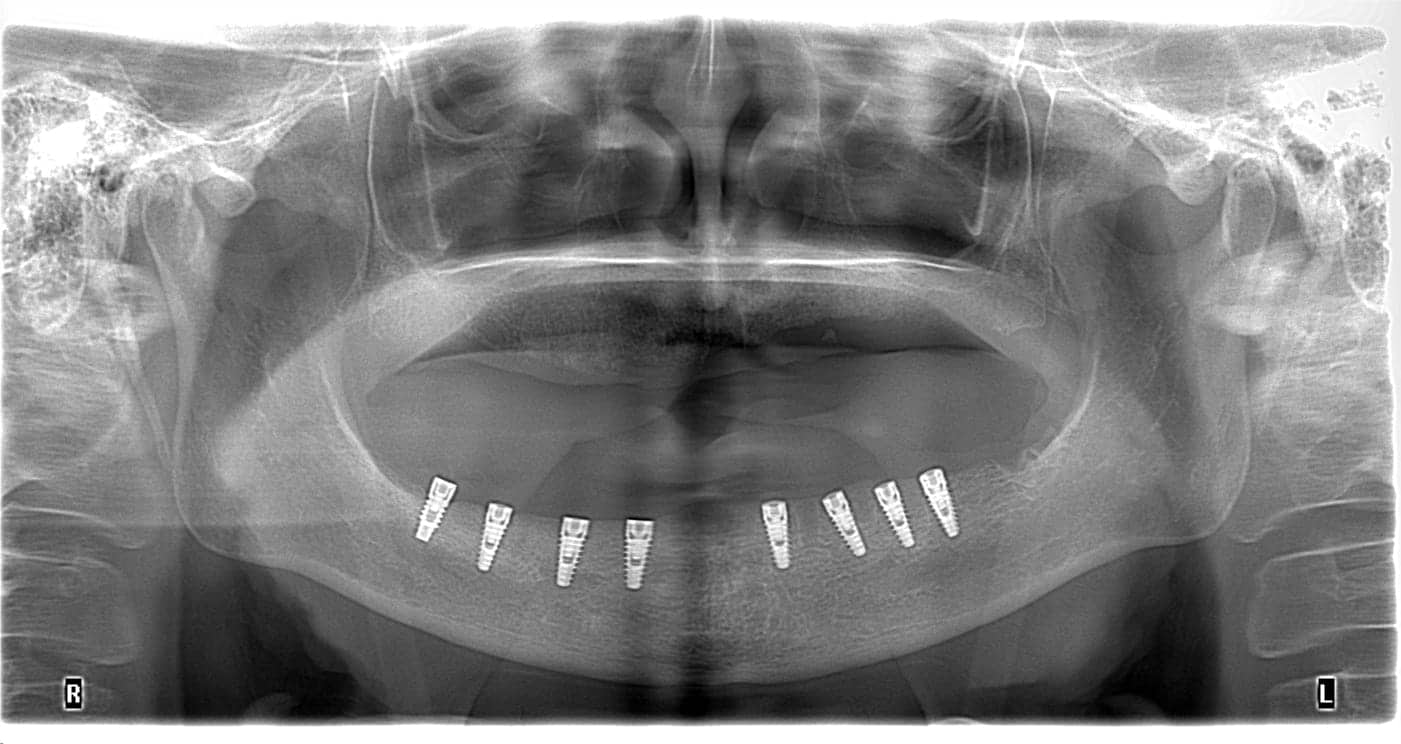

Dacă implantul nu se integrează sau observi mobilitate persistentă, medicul va evalua situația prin:

• radiografii panoramice sau CBCT;